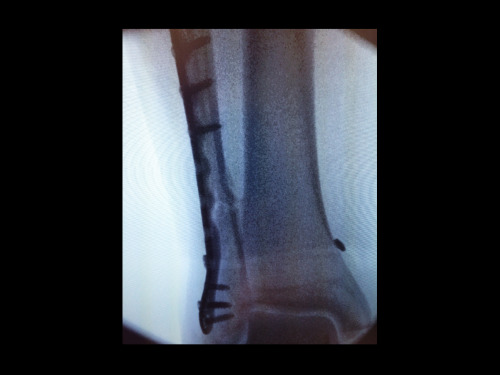

Luego, directo al hospital para radiografías, donde finalmente vimos la magnitud de los daños. Fue entonces cuando las cosas se pusieron realmente reales. Me dijeron que necesitaba cirugía para reparar la fractura. Decidí volar de regreso a Londres y encontrar un médico que pudiera verme lo antes posible. (¡Gracias por la recomendación, Paul!) Una resonancia magnética y unas radiografías, fijó una fecha y prepararon la operación.

Así que ... aquí estoy, recuperándome con 6 tornillos de metal en mi pierna, pensando en la vida y en la TSA de aquí a Kalamazoo ... demonios.